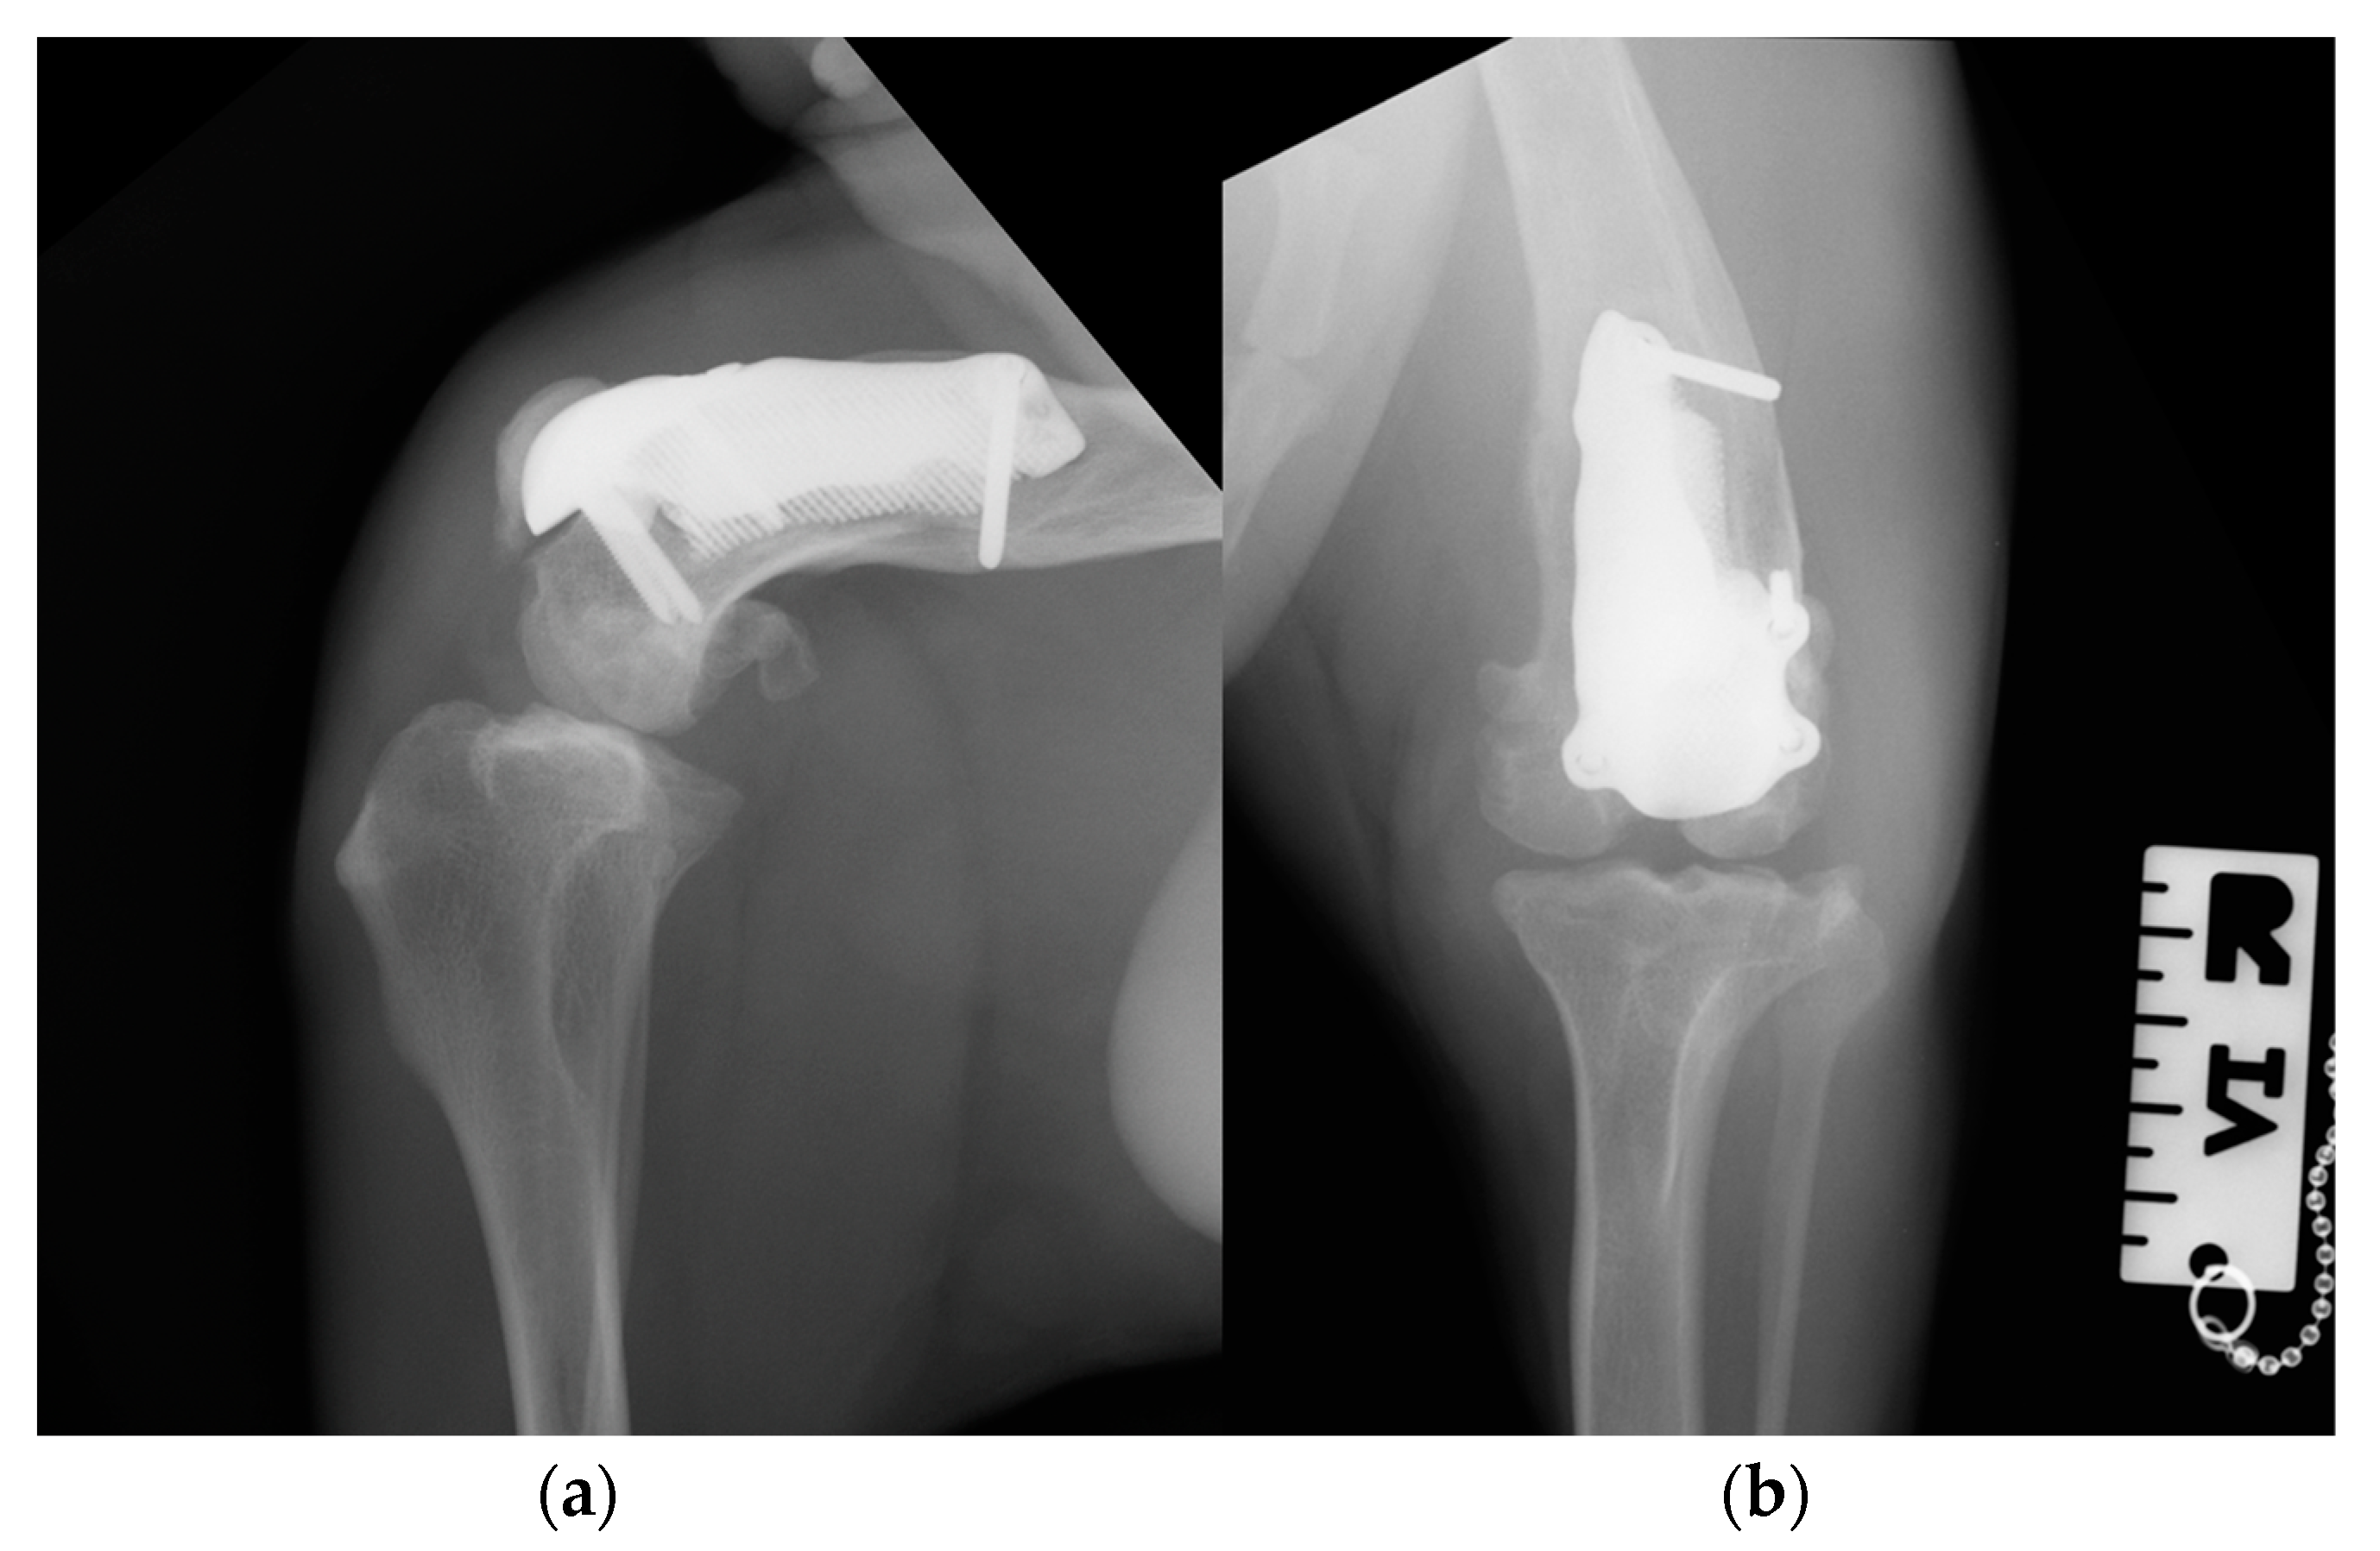

Figure 10. Postoperative medio-lateral (a) and caudo-cranial (b) radiographs of the stifle joint showing the appropriate prosthesis position, the correct length of the screws and the reduction in the patella.

Postoperative medio-lateral and caudo-cranial radiographs of the stifle joint were performed to evaluate the proper prosthesis position and the length of the screws and to confirm the patellar reduction (Figure 10). To improve the postoperative assessment, CT scans of the right stifle joint were obtained. A modified Robert Jones splint was applied for 24 h postoperatively. Meloxicam (0.1 mg/kg) once a day and amoxicillin and clavulanic acid (20 mg/kg) twice a day were prescribed for 10 days, pending the results of a bacteriological examination, and only short walks on the leash to be gradually increased during the two months of postoperative rehabilitation were recommended. After 5 days, the bacteriological exam results were negative, and the antibiotic therapy was continued as indicated previously.